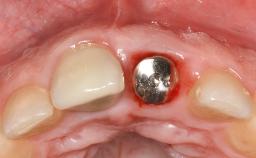

Peri-Implant Tissue Health

Maintenance of healthy peri-implant soft tissue as well as supporting peri-implant bone is an essential part of long-term success of implant therapy. An accurate maintenance protocol of peri-implant tissue health may prevent biological complications such as peri-implantitis. After the delivery of the prosthesis, patients should be followed up and clinical and radiological examinations should be performed on a regular basis to detect any etiological factors that may lead to such complications. This topic discusses properties of healthy and pathological conditions of peri-implant tissue, clinical and radiological examination methods of peri-implant tissue, as well as protocols for maintaining peri-implant tissue health.